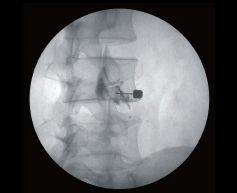

- Фиксация одним движением

Вся система фиксации спроектирована по принципу одного движения, что делает навигацию С-дуги очень простой и удобной. - Лазерный маркер наведения

Данная функция позволяет сократить время экспозиции и дает возможность быстрого позиционирования в случае необходимости частого перемещения по операционному полю, что в способствует снижению лучевой нагрузки на пациентов и медицинский персонал. - ЖК-дисплей и сенсорные кнопки управления

Сенсорный кнопки управления объединены с экраном, что делает более удобным навигацию в меню и ввод новых параметров. - Анатомически программируемая рентгенография (APR)

Анатомические программы (APR) позволяют максимально ускорить выполнение рутинных операций и позволяет проводить различные виды исследований. - Станция обработки изображения с 2-мя монохромными мониторами

Продвинутая система управления и обработки информации, расширяющая возможности С-дуги. Емкая база данных сохраненных изображений позволяет проводить быстрый поиск и просмотр изображений, кроме того система может легко включаться в общебольничную сеть (PACS) благодаря использованию стандарта DICOM 3.0. Данная система существенно облегчает работу врача и позволяет давать более объективные заключения. - Множество различных инструментов для работы с изображением